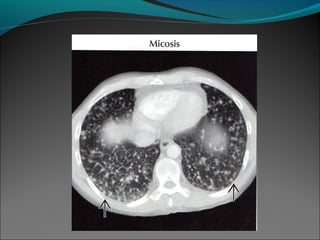

La apariencia de

las opacidades

circulares que

representan los

bronquios

dilatados llenos

de moco o pus es

un signo de

bronquiectasia

manifiesta, y se

ve casi siempre

en presencia de

otros bronquios

obviamente

dilatados,

algunos de los

cuales pueden

contener nivel

aire-líquido.

La apariencia de lasopacidades circulares que representan los bronquios dilatados llenos de moco o pus es un signo de bronquiectasia manifiesta, y se ve casi siempre en presencia de otros bronquios obviamente dilatados, algunos de los cuales pueden contener nivel aire-líquido.